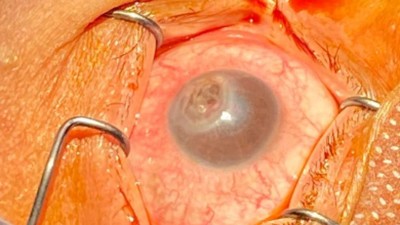

Can steroid abuse and malnutrition cause corneal melting?

10 years after bariatric surgery and extensive weight loss, a 27-year-old took prednisolone to regain weight. But 3 months later, she presented with corneal melting and perforation.

Boy looking unhappy/© airdone / iStock / Getty Images Plus (symbolic image with model), Older man trying to sleep/© amenic181 / Getty Images / iStock (symbolic image with model), Brain inside a medicine capsule/© Jorg Greuel / Getty Images, Speech therapy/© wanderluster / Getty Images (symbolic image with models), Ocular examination of patient with corneal melting/© 2025, Rawan Hosny et al, BMC Ophthalmol, Human brain illustration/© (M) CHRISTOPH BURGSTEDT / SCIENCE PHOTO LIBRARY / Getty Images, Head with puzzle pieces/© Berit Kessler / Generated with AI / stock.adobe.com, Woman at a medical consultation/© Antonio_Diaz / iStock / Getty Images Plus (symbolic image with models), Older Black man exercising at the seaside/© JLco - Julia Amaral / Getty Images / iStock (symbolic image with model), Neuropathological findings in iatrogenic cerebral amyloid angiopathy/© 2025, Ana Sofia Costa et al, Neurol Res Pract, A fragment of sponge extracted from the esophagus and an endoscopic view of ulcer formation within the hernial sac/© (M) 2025, Keisuke Ojiro et al, Clin J Gastroenterol, under exclusive licence to the Japanese Society of Gastroenterology, Medicine Matters Podcast promo image/© Springer Medizin GmbH, Navigating neuroimaging in Alzheimer’s care: Practical applications and strategies for integration/© Springer Healthcare IME, Alzheimer’s disease in the biomarker era: preparing the multidisciplinary care team/© Springer Healthcare IME, EAMN Logo/© Springer Healthcare IME